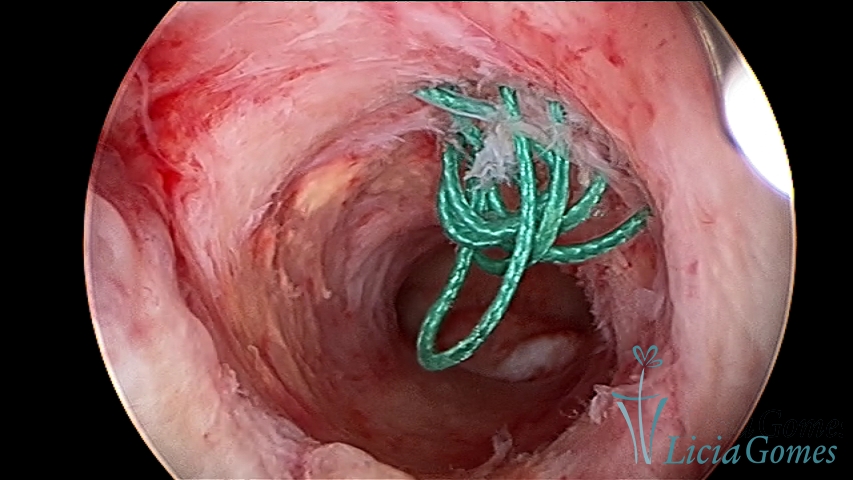

Pólipo uterino envolto em fio do DIU